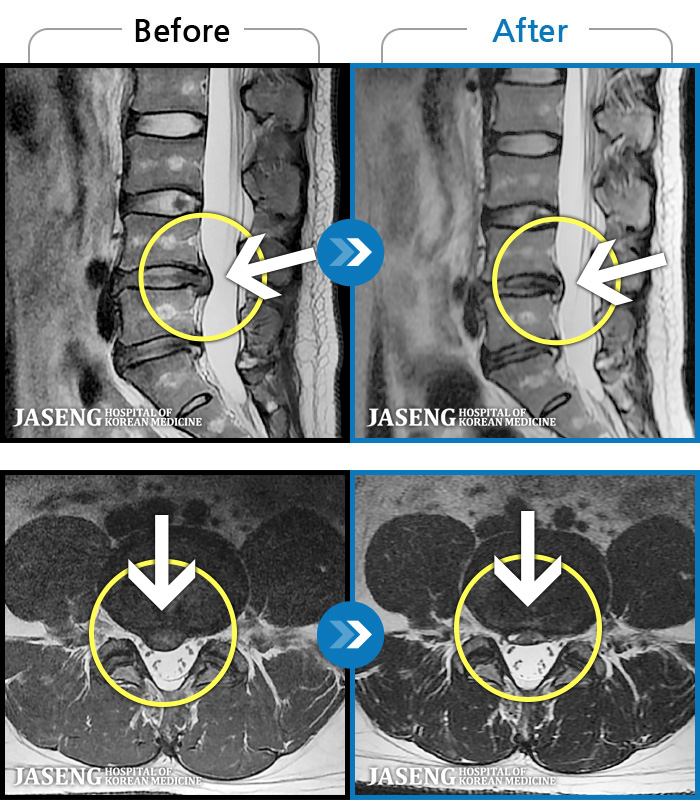

[뱸] 19.11.28~25.05.06